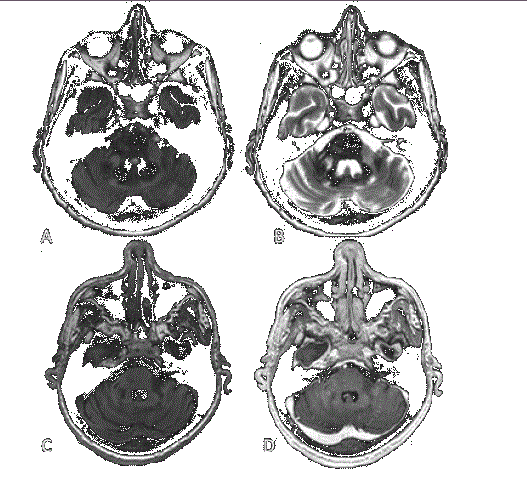

Hombre de 57 años con diagnóstico de VIH desde hace 8 años; estuvo con tratamiento antirretroviral durante 4 años y, posteriormente lo suspendió. Tres semanas antes de llegar con nosotros, reinició tratamiento antirretroviral. Este caso presenta datos diagnósticos y terapéuticos importantes de LMP secundaria al síndrome de reconstitución inmunológica y con afectación cerebelosa aislada, escenario que solo se encuentra en el 10% de todos los casos. Imagen 1. Resonancia magnética de encéfalo hipointensas en secuencia T1 sin reforzamiento en la secuencia T1 poscontraste.

Realizamos resonancia magnética de encéfalo con medio de contraste (gadolinio) documentando cambios en la intensidad de señal en secuencias T2 y FLAIR, infratentoriales, hacia los pedúnculos cerebelosos; lesión nodular derecha con restricción en difusión/ADC (Imagen 1). La lesión cerebelosa izquierda fue la de mayor tamaño (Imagen 2); ninguna de las lesiones presentó reforzamiento con el paso de medio de contraste y, a pesar de la extensión de las lesiones, no se documentó efecto de masa sobre las estructuras adyacentes. Estos hallazgos suguirierón leucoencefalopatía multifocal progresiva.

Imagen 1A y B . Muestran lesiones hiperintensas en secuencias FLAIR y T2, sin restricción a la difusión (no se muestra DWI) ni efecto de masa; C y D. Lesiones